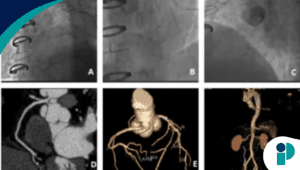

Trombosis biventricular tras infarto silente sorprende a clínicos

Un infarto de miocardio no siempre se presenta con dolor torácico clásico, pero puede desencadenar complicaciones potencialmente mortales. En este reporte, los médicos documentan el caso de un hombre de